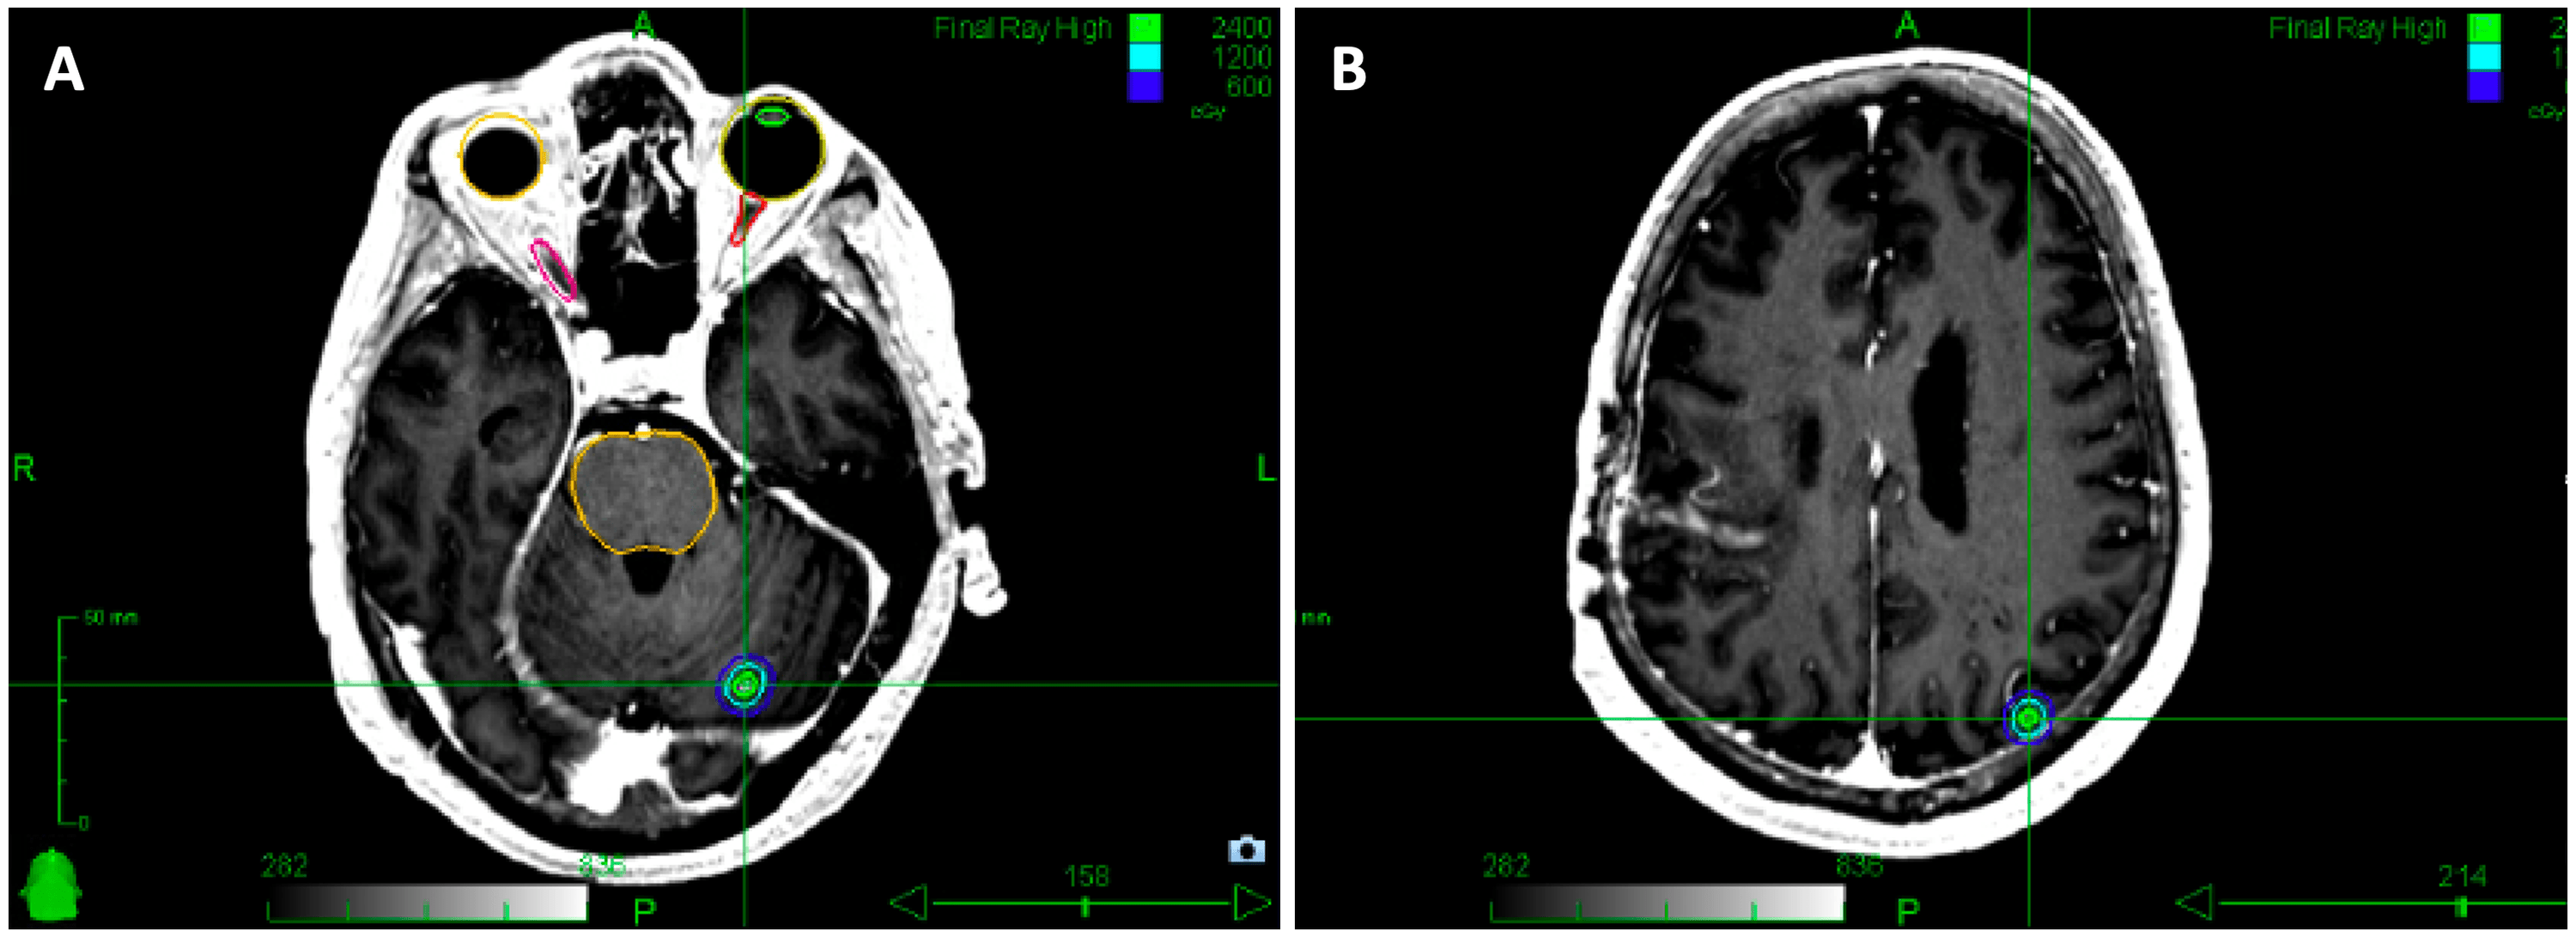

Cavitydirected stereotactic radiosurgery (SRS) treatment. Illustrated Stereotactic Radiosurgery To Brain Metastases Radiation and steroid dosing can affect the immune composition of brain metastasis (bm). The authors have designed a. Treatment of bm ranges from supportive care to multimodal strategies considering surgery, fractioned radiotherapy,. Brain metastases are the most common intracranial malignancy and remain a substantial source of morbidity and mortality in. Stereotactic radiosurgery (srs) is a mainstay treatment option for brain. Stereotactic Radiosurgery To Brain Metastases.